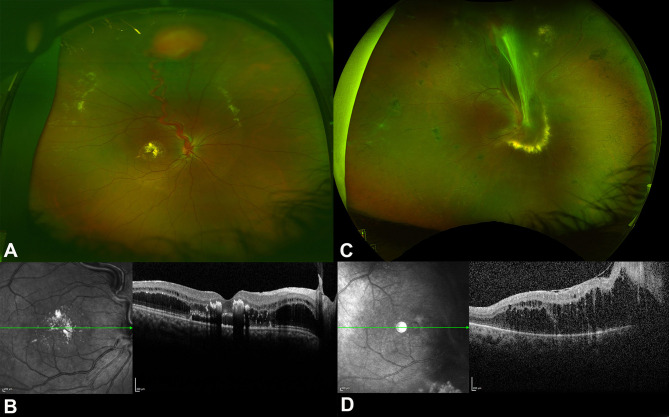

The clinical features and real world treatment outcomes in von Hippel Lindau related retinal capillary hemangioblastomas.

von Hippel - Lindau相关性视网膜毛细血管母细胞瘤的临床特征及实际治疗结果。